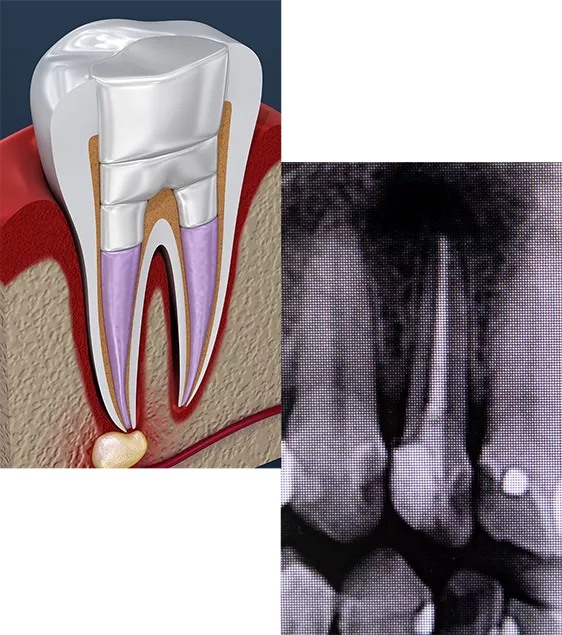

Endodnotics is commonly known as a root canal. It involves the removal of the pulp of the tooth.

By removing the infected inner tissue—the pulp—of the tooth with a root canal, we both treat the current infection and help prevent a future infection. Since an infection can spread to other tissues surrounding the infected tooth, immediate action is important.

The root canal process begins by drilling a small hole in the tooth, through which the dentist removes the inner pulp. The dentist then seals this hole, or may choose to restore the tooth with a dental crown. Since we give every patient a local anesthetic before treatment—just like with fillings—patients typically don’t feel a thing.